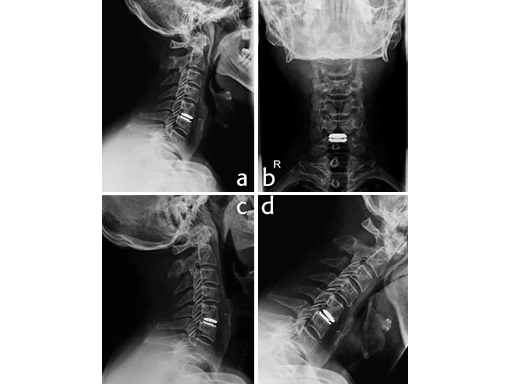

A microsurgical discectomy, decompression and implantation of a Prodisc-C Vivo implant was performed (Fig. 2a-b).

The early and 6 month outcome was excellent. The segment showed preserved mobility (Fig. 2c extension and Fig. 2d flexion). The patient returned to work after two weeks and returned to normal activities.